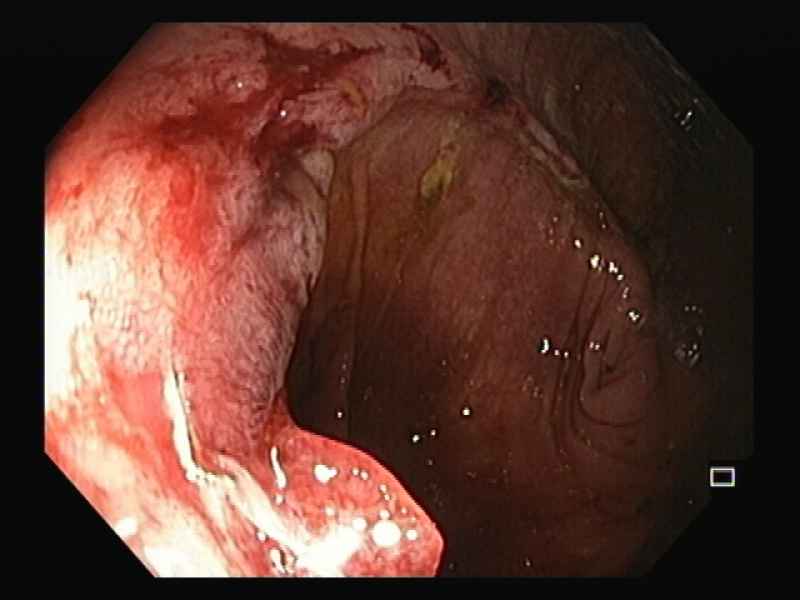

Intraductal Papillary Mucinous Neoplasm of the pancreas with gastric fistula

Fotografia